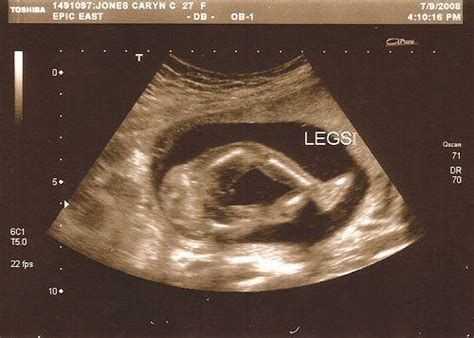

1、超声波扫描:目前为止它对胎儿没有不良影响,因此在妇产科界使用非常普遍。